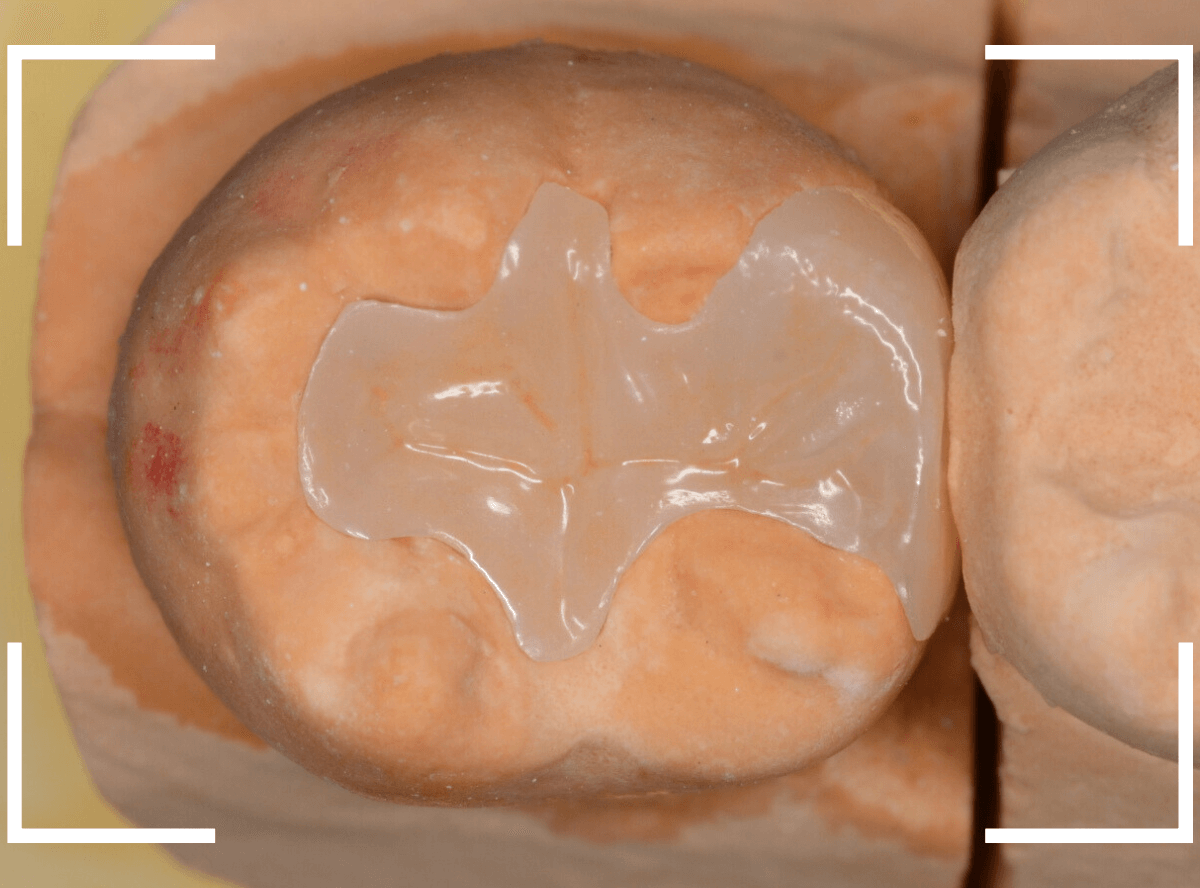

模型上で精密に製作します。

治療後の状態です。

自然な仕上がりで、患者さんにもご満足いただけました。